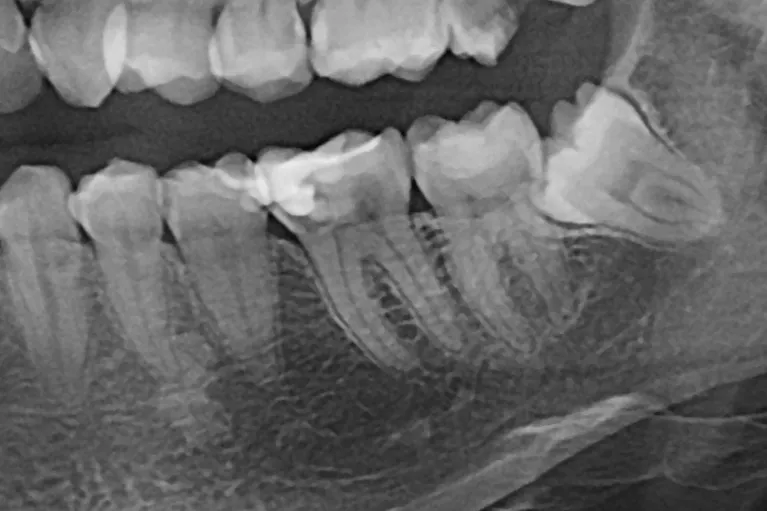

0 – Radiografie inițială